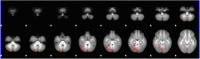

Expanding behavioral and neurobiological evidence affirms benefits of shared (especially parent-child) reading on cognitive development during early childhood. However, the majority of this evidence involves factors under caregiver control, the influence of those intrinsic to the child, such as interest or engagement in reading, largely indirect or unclear. The cerebellum is increasingly recognized as playing a "smoothing" role in higher-level cognitive processing and learning, via feedback loops with language, limbic and association cortices. We utilized functional MRI to explore the relationship between child engagement during a mother-child reading observation and neural activation and connectivity during a story listening task, in a sample of 4-year old girls. Children exhibiting greater interest and engagement in the narrative showed increased activation in right-sided cerebellar association areas during the task, and greater functional connectivity between this activation cluster and language and executive function areas. Our findings suggest a potential cerebellar "boost" mechanism responsive to child engagement level that may contribute to emergent literacy development during early childhood, and synergy between caregiver and child factors during story sharing.